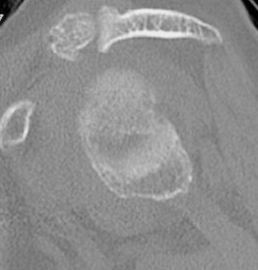

Type A2 Type B1

Type B2 Type B3

Type B3